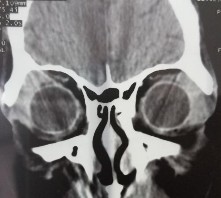

Bệnh nhân nam, 41 tuổi, MP: lồi mắt

Chẩn đoán MP: U hỗn hợp tuyến lệ lành tính

Bệnh nhân lồi mắt xuất hiện 3 năm, tăng nhanh trong vòng 1 năm trước vào viện, đẩy nhãn cầu xuống dưới (A). Hình ảnh cắt lớp vi tính có khối tăng ti trọng, bờ dày đều, kích thước 27 x 38 mm (C, D). Bệnh nhân được phẫu thuật cắt bỏ u cả khối gồm cả vỏ (E). Kết quả giải phẫu bệnh là hình ảnh biểu mô và trung mô của u hỗn hợp tuyến lệ lành tính (F: H&E x 100).